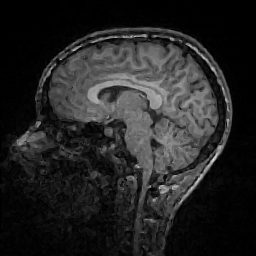

Improving image reconstruction from a sparse set of known pixels was the main motivation behind our work. Therefore, we applied it to two well-known natural images, lena and peppers, as well as to a medical image, a slice of a weighted brain MR scan (t1slice). For lena, we kept a random subset of only of the pixels. Due to the lower resolution of the peppers and t1slice images, we kept and , respectively.

Results for lena are shown in Figure 2, for peppers in Figure 3, and for t1slice in Figure 4. A quantitative evaluation in terms of MSE and AAE is presented in Table 4.1. In terms of the numerical results, our proposed method produced a more accurate reconstruction than any of the competing approaches. Visually, there is a clear difference between second-order (EED) and fourth-order approaches (Li1, Li2, FOEED). Especially, we found that the shapes of edges were reconstructed more accurately. For example, we noticed this around the shoulder and hat in the lena image (Figure 2). Similarly, the white and grey matter boundaries were better separated in the t1slice (Figure 4).

| t1-slice | MSE | 166.356 | 150.002 | 152.698 | 155.955 |

| AAE | 5.895 | 5.698 | 5.789 | 5.853 |

| t1-slice | MSE | 114.845 | 107.323 | 24.74 (FOEED) |

| AAE | 4.610 | 4.553 | 10.64 (EED) |